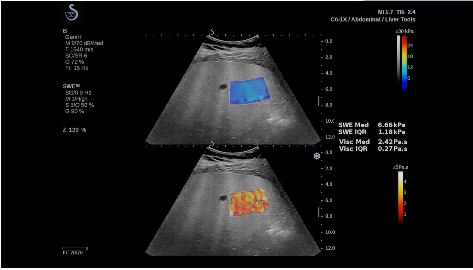

法國(guó)聲科影像(SuperSonic Imagine,SSI. Euroniex:FR0010526814)近日發(fā)表公告,宣布其研發(fā)的新一代“極速”超聲成像平臺(tái)(UltraFast Imaging),首次實(shí)現(xiàn)了肝臟的多項(xiàng)超聲定量評(píng)估新指標(biāo)同步檢測(cè),包括:Att PLUS,SSp PLUS和Vi PLUS等,基本涵蓋肝臟相關(guān)病理變化指征的如纖維化、脂肪變、炎癥等。據(jù)悉,此多項(xiàng)新技術(shù)新將搭載于新Aixplorer系列E超系統(tǒng)。

法國(guó)聲科影像公司(SuperSonic Imagine. SA,F(xiàn)rance),2005年由三位諾貝爾獎(jiǎng)級(jí)科學(xué)家主導(dǎo)創(chuàng)立,專(zhuān)注于E超的開(kāi)發(fā)和生產(chǎn),是目前世界上唯一可以同時(shí)應(yīng)用兩種波進(jìn)行人體檢測(cè)的系統(tǒng):縱波形成高質(zhì)量的二維組織結(jié)構(gòu)圖像,而橫波可以使醫(yī)生實(shí)時(shí)準(zhǔn)確地看到并分析組織的硬度,有效減少有創(chuàng)檢查、避免損傷。

E超相關(guān)技術(shù)已被多項(xiàng)多中心大樣本研究證實(shí)對(duì)于肝纖維化無(wú)創(chuàng)評(píng)估有重要意義,同時(shí)也可全面應(yīng)用于乳腺、甲狀腺、肝臟、前列腺、肌骨、婦科等全身各組織器官的定量評(píng)估和鑒別診斷。在慢性肝臟方面,聲科E超的肝臟相關(guān)定量診斷技術(shù)集,于2018年獲得美國(guó)FDA認(rèn)證,成為FDA歷史上首次獲批的單病種超聲全面定量解決方案。